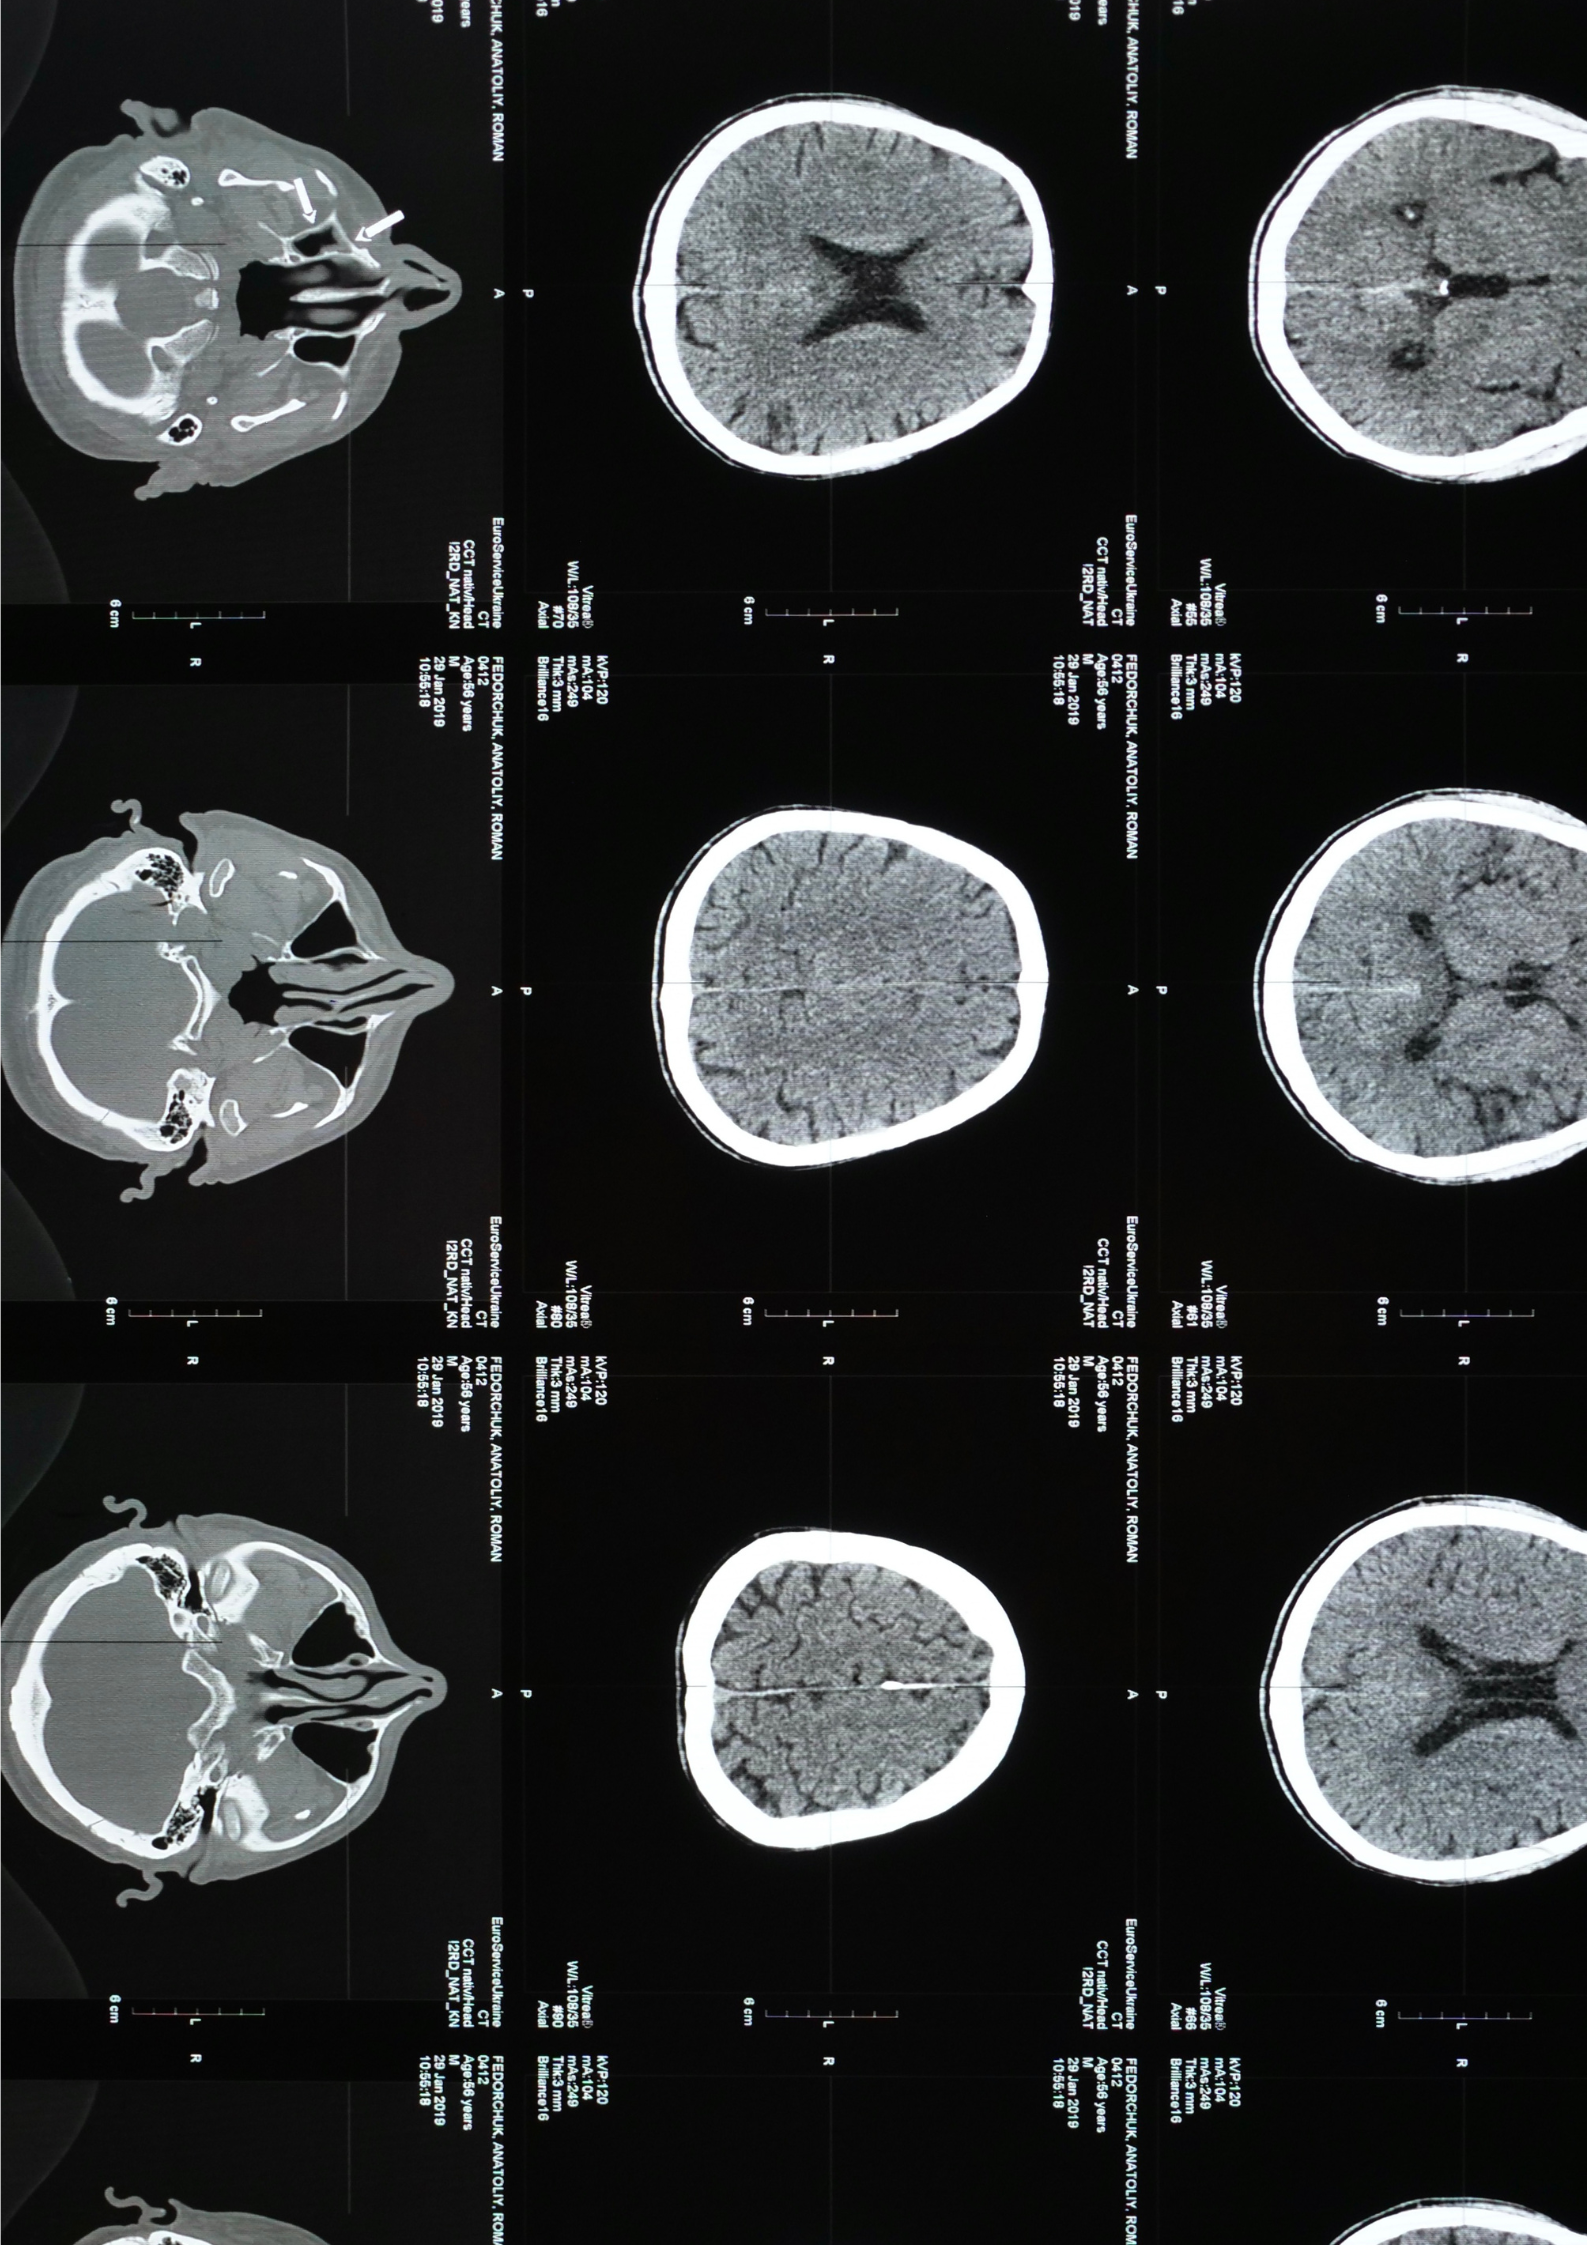

This study adds an important piece to that puzzle, showing how brain connectivity patterns differ depending on when alcohol use is initiated and how much is consumed.